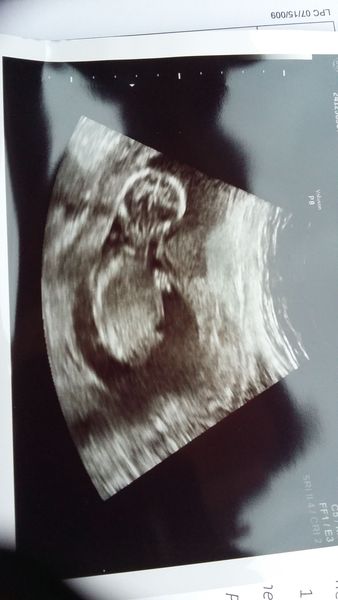

haveacupoftea · 05/12/2016 11:52

Scan today at 14+3! Most enjoyable one so far, saw baby and heartbeat straight away and she didn't have to delve into my knickers to find the baby Grin

Due in June, 12 week scans happening and coming up!